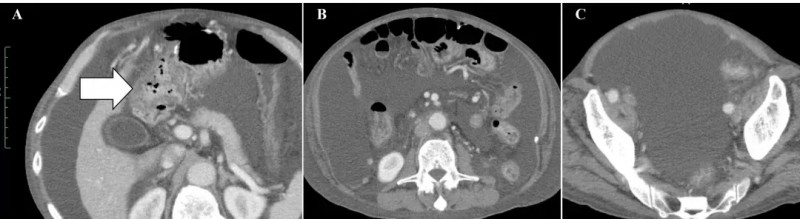

《Cureus》报道的案例显示,WT1/MUC1肽脉冲树突状细胞(DC)联合CD3激活T淋巴细胞(CAT)的过继细胞疗法(ACT),成功实现晚期十二指肠癌患者长期疾病控制——截至首次给药后54个月,肿瘤无复发进展。

治疗前后变化显著:治疗前,腹部CT可见十二指肠周围大网膜明显扩张(详见下图A箭头所示),且存在大量恶性腹水(详见下图B、C)。

完成8次治疗后1个月,患者症状与影像学表现均大幅改善:恶性腹水完全消退,腹胀、腿部水肿消失,食欲恢复,原发病灶及转移性淋巴结持续缩小,腹膜播散的影像学特征已不明显,腹腔内大网膜(脂肪性粘稠组织)消失(详见下图A),仅右侧腹股沟疝因既往大量腹水导致的腹压影响仍持续存在(详见下图C)。此外,治疗无严重不良反应,患者恢复正常活动,截至首次给药后54个月仍无复发。